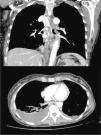

Mujer de 60 años, exfumadora, diagnosticada de adenocarcinoma de ovario en tratamiento con quimioterapia, que presentaba disnea súbita, pesadez de miembros superiores y síncope. A la exploración destacaba tensión arterial 110/60mmHg, frecuencia cardiaca 110lpm, saturación de oxígeno del 95%, con eritema y edema facial, sin signos de circulación colateral ni adenopatías. En la analítica solo destacaba hemoglobina de 8,6g/dl. La angio-TAC de tórax evidenciaba una trombosis extensa a nivel de la vena ácigos y hemiácigos, sin signos de TEP ni SVC (fig. 1). Tanto la ecografía de miembros inferiores como el ecocardiograma no mostraron hallazgos de interés. El estudio de trombofilia, incluyendo los anticuerpos antifosfolípidos fueron negativos. La paciente recibió tratamiento con tinzaparina ajustada al peso, decidiéndose mantener la anticoagulación hasta la finalización de la QT (9 meses), con completa resolución de la sintomatología respiratoria y sin evidenciar complicaciones, apreciando en la TAC de seguimiento re-permeabilización de la TVA.

Para el diagnóstico de la TVA, la angio-TAC de tórax es la prueba de elección, valorando la realización de una flebografía-TAC si existe sospecha de SVC. En los AVA trombosados, se ha sugerido el uso de la TC-multidetector dinámico con ECG permitiendo la valoración del daño miocárdico5.